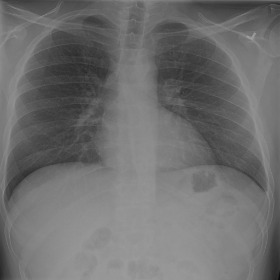

Fig. 3 shows image samples from the above datasets.

Refer to caption

(a)

(b)

(c)

(d)

Figure 3: Image diversity across four datasets: (a) JSRT, (b) Montgomery County X-ray, (c) NIH ChestX-ray14, and (d) CheXpert